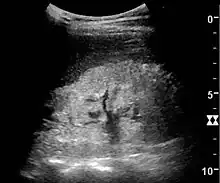

Ultrasound

Kidney ultrasonography is useful for diagnostic and prognostic purposes in chronic kidney disease. Whether the underlying pathologic change is glomerular sclerosis, tubular atrophy, interstitial fibrosis, or inflammation, the result is often increased echogenicity of the cortex. The echogenicity of the kidney should be related to the echogenicity of either the liver or the spleen (Figure 22 and Figure 23). Moreover, decreased kidney size and cortical thinning are also often seen and especially when disease progresses (Figure 24 and Figure 25). However, kidney size correlates to height, and short persons tend to have small kidneys; thus, kidney size as the only parameter is not reliable.[54]

Chronic renal disease caused by glomerulonephritis with increased echogenicity and reduced cortical thickness. Measurement of kidney length on the US image is illustrated by '+' and a dashed line.[54]